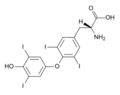

- 220px-Magnesium pyridoxal 5-phosphate glutamate.png سلام المجذوب

05:23، 10 سبتمبر 2012

220 × 158؛ 6 كيلوبايت